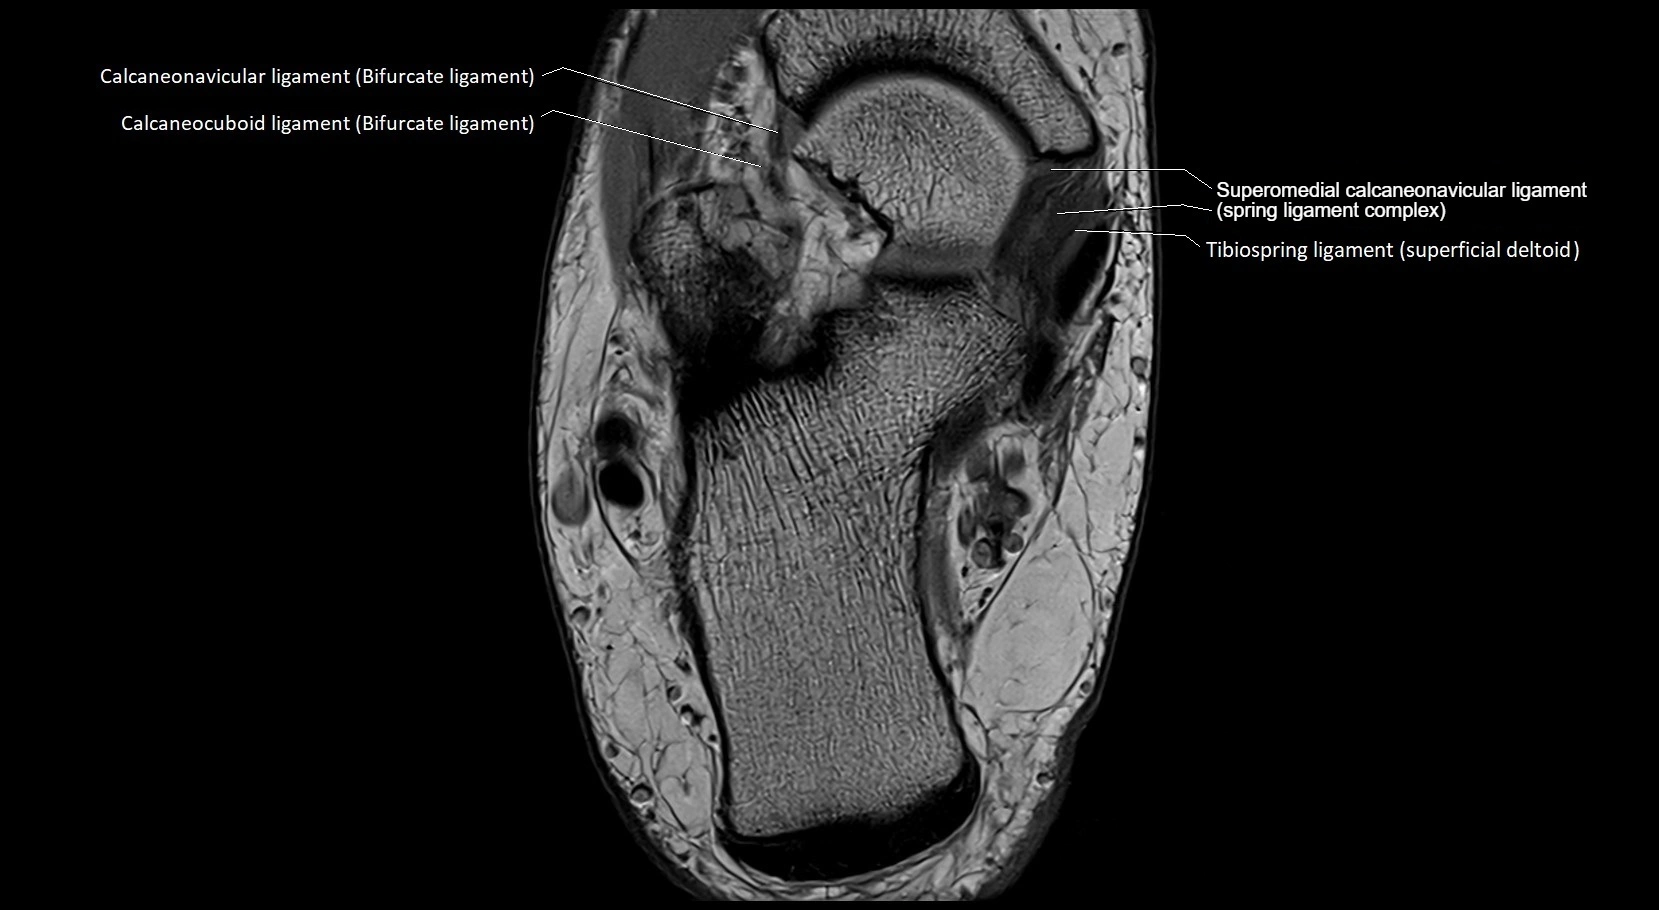

MRI image

image